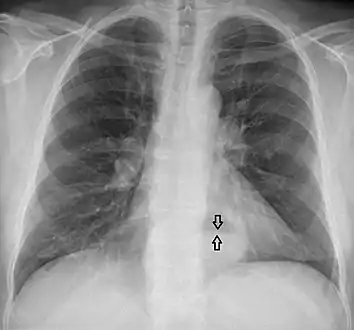

Diagnosis

The diagnosis of a hiatal hernia is typically made through an upper GI series, endoscopy, high resolution manometry, esophageal pH monitoring, and computed tomography (CT). Barium swallow as in upper GI series allows the size, location, stricture, stenosis of oesophagus to be seen. It can also evaluate the oesophageal movements. Endoscopy can analyse the esophageal internal surface for erosions, ulcers, and tumours.

Meanwhile, manometry can determine the integrity of esophageal movements, and the presence of esophageal achalasia. pH testings allows the quantitative analysis of acid reflux episodes. CT scan is useful in diagnosing complications of hiatal hernia such as gastric volvulus, perforation, pneumoperitoneum, and pneumomediastinum.[8]